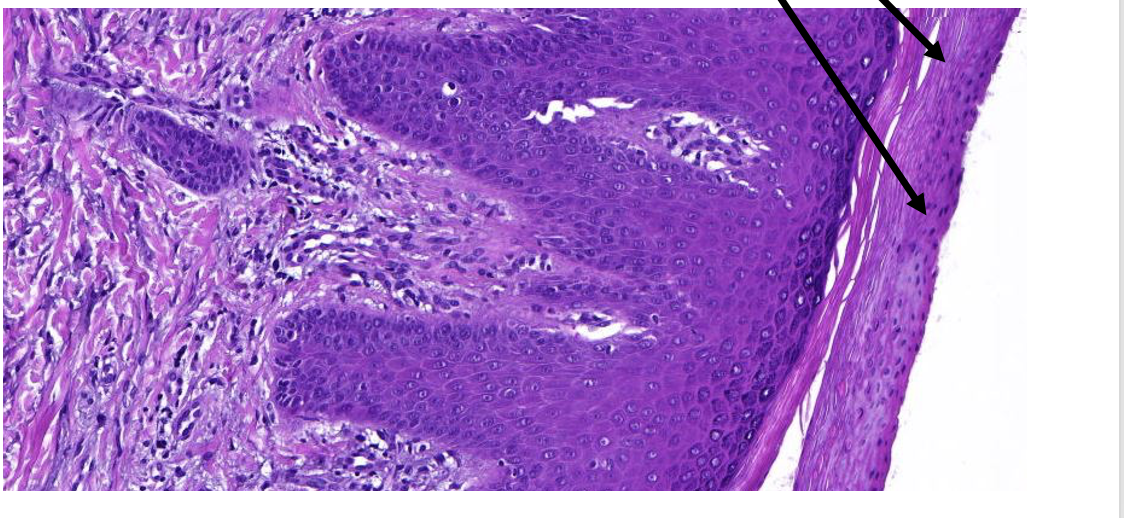

welk orgaan

prostaat hypertrofie

pathologische kenmerken prostaat hypertrofie

ipv lobulaire—> nodulaire indeling, omgeven door bindweefsel

bevat gedilateerde klierbuizen

vorming van cysten (cysteuze dilatatie)

toename stroma, glad spierweefsel en lymfocyten